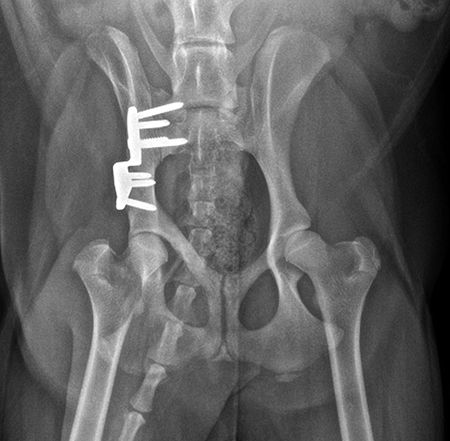

Postoperative radiographs revealed reduction in subluxation with capture of the femoral head in the right coxofemoral joint (Fig 4). Palpation of the hip revealed good stability of the right hip. Activity was restricted to leash walk only for 6 weeks postoperatively. Radiographic examination 7 weeks following surgery revealed healing of the ilial osteotomy, stable implants, and excellent coxofemoral conformation and stability (Fig 5).

Radiographic examination at 6 months postsurgery revealed stable implants, excellent coxofemoral conformation, and no evidence of osteoarthritis of the right hip. The left acetabulum was mildly shallow and mild subluxation of the femoral head was present at follow-up examination (Fig 6). Early osteophytosis in the region of the left femoral neck was evident. The dog was using the right hind leg normally and was showing no signs of instability or pain of the right hip. Mild instability and pain of the left hip was present on palpation. The dogs left hip was treated with a joint supplement and NSAIDs as needed. Future THR will be performed if clinical signs no longer respond to medical treatment.